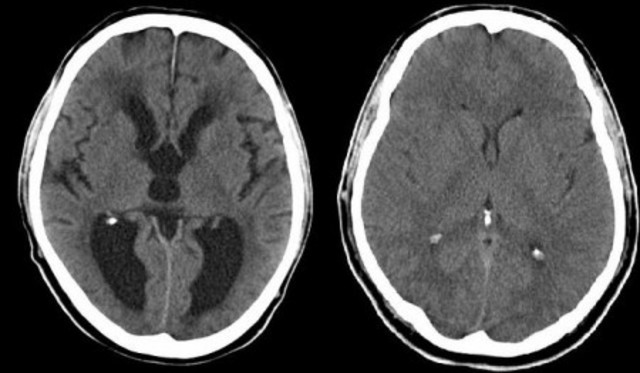

Ressonancia magnetica tomografia computadorizada